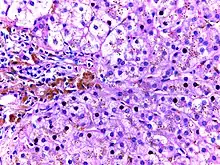

![]() | Tumor giant cell | Malignant neoplasm showing marked anaplasia. Note the marked nuclear pleomorphism, bizarre cells and tumor giant cells. | Category: Histopathology of giant cell tumors | Giant cell tumor |